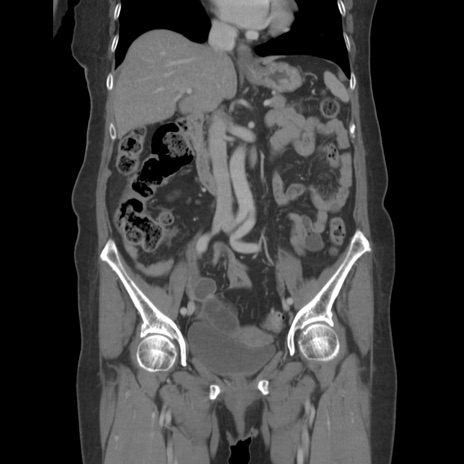

症例19(冠状断像)

【症例】80歳代女性

【主訴】下腹部痛

【現病歴】約8時間前より下腹部痛の出現あり、救急外来受診。

【既往歴】両側付属器切除

【身体所見】意識清明、下腹部正中に手術痕あり、その部位に一致して圧痛と反跳痛あり。腸蠕動音は亢進。

【データ】WBC 9300、CRP 0.15